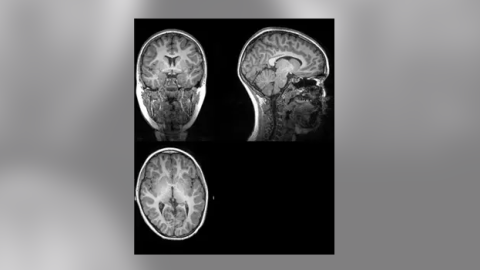

El coronavirus altera el volumen de materia gris en el cerebro, según un estudio

Los pacientes con covid-19 que reciben oxígeno o experimentan fiebre muestran un menor volumen de materia gris en la red frontal-temporal del cerebro, según un nuevo estudio dirigido por investigadores de la Universidad Estatal de Georgia y el Instituto Tecnológico de Georgia (Estados Unidos). El estudio, publicado en la revista Neurobiology of Stress, ha evidenciado que un menor volumen de materia gris en esta región del cerebro se asociaba a un mayor nivel de discapacidad entre los pacientes con covid-19, incluso seis meses después del alta hospitalaria.